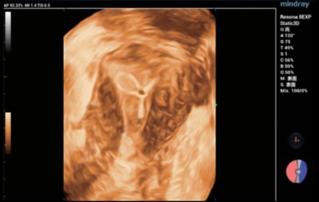

Endocavity 볼륨 볼록 배열 변환기(DE10-3WU, Resona 7, Mindray)를 이용한 초음파 검사에서 좌우 양쪽 항문거근(Levator ani nuscle)의 찢김이 관찰됨. 회음부의 힘줄 중심이 3~4mm로 얇아지고, 거근틈(levator hiatus) 거리 증가 - 6.13cm, LUG1(요도와 m 사이의 거리. Bulbocavernosus) – 2.95cm 및 LUG2 – 3.15cm(보통 2.5cm 미만)

형상 1. 외부생식기에서 3등급의 방광탈(cystocele)과 양쪽 항문거근(m. levatorani)의 찢김이 확인된 49세 환자 R, 안정상태에서 강내 센서를 사용한 골반바닥의 3D 재구성 초음파(A)와 Valsalva 검사(B)